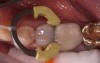

Fig 13. Preoperative view of a patient who presented with a failing posterior composite restoration that would be replaced with a dual-cured dentin and enamel replacement bulk-filled composite.

Figure 13

Fig 14. The defective restoration was removed; a sectional ring was placed to ensure good, tight contact when placing the lower viscosity bulk fill, as well as ideal separation of tooth structure for proper adaptation; glass ionomer was placed for pulpal protection.

Figure 14

Fig 15. The nanofilled, low viscosity dual-cured bulk-fill composite was placed from the bottom to top of the preparation, excess was wiped off, and the material was allowed to self-cure between 2 and 4 minutes. A 30-second light-cure was performed after self-curing.

Figure 15